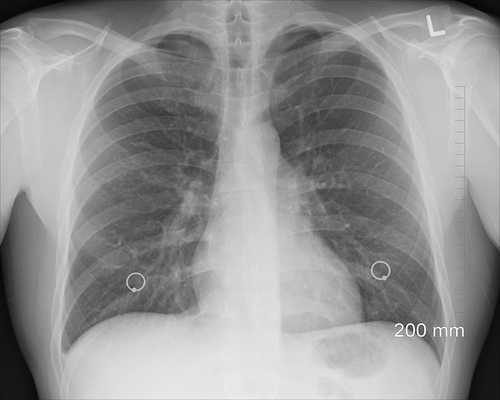

Пары диацетила попадают в легкие, вызывая поражение бронхиол, при котором их просветы закрываются.

Если вы представляете себе свои легкие как дерево, то маленькие воздушные ответвления, или бронхиолы, — это самый дальний конец самых маленьких ветвей, удаленных далеко от основного ствола.

Это — то место, где кислород попадает в кровь, а углекислый газ (CO2) выходит. Ткань в бронхиолах становится фиброзной, в основном состоящей из рубцовой ткани.

Легкие прекращает работать, как нужно, и все меньше и меньше кислорода поступает из легких в кровоток.

Когда процесс рубцевания произошел, он остается навсегда — ткани никогда не станут прежними.

В медицине эта болезнь описывается как облитерирующий бронхиолит или диацетиловый облитерирующий бронхиолит.

- Легкие: возникает сухой кашель, одышка и свистящее дыхание. Симптомы могут развиваться постепенно, или возникнуть быстро и внезапно. Лекарства от астмы не эффективны.

- Прогрессирование заболевания происходит от нескольких месяцев до нескольких лет и приводит к поражению дыхательных путей и потере функций вентиляции легких.

Болезнь легких трудно диагностировать даже опытным пульмонологам. И врачи, имеющие опыт лечения профессиональных заболеваний, могут пропустить облитерирующий бронхиолит.

Существует все больше научных доказательств того, что воздействие диацетилом вызывает тяжелую болезнь легких, называемую облитерирующим бронхиолитом.